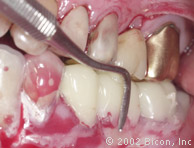

19. | 图示种植体内径及其软组织龈沟,以及与三单位固定桥分离的磨牙上的全冠。 |